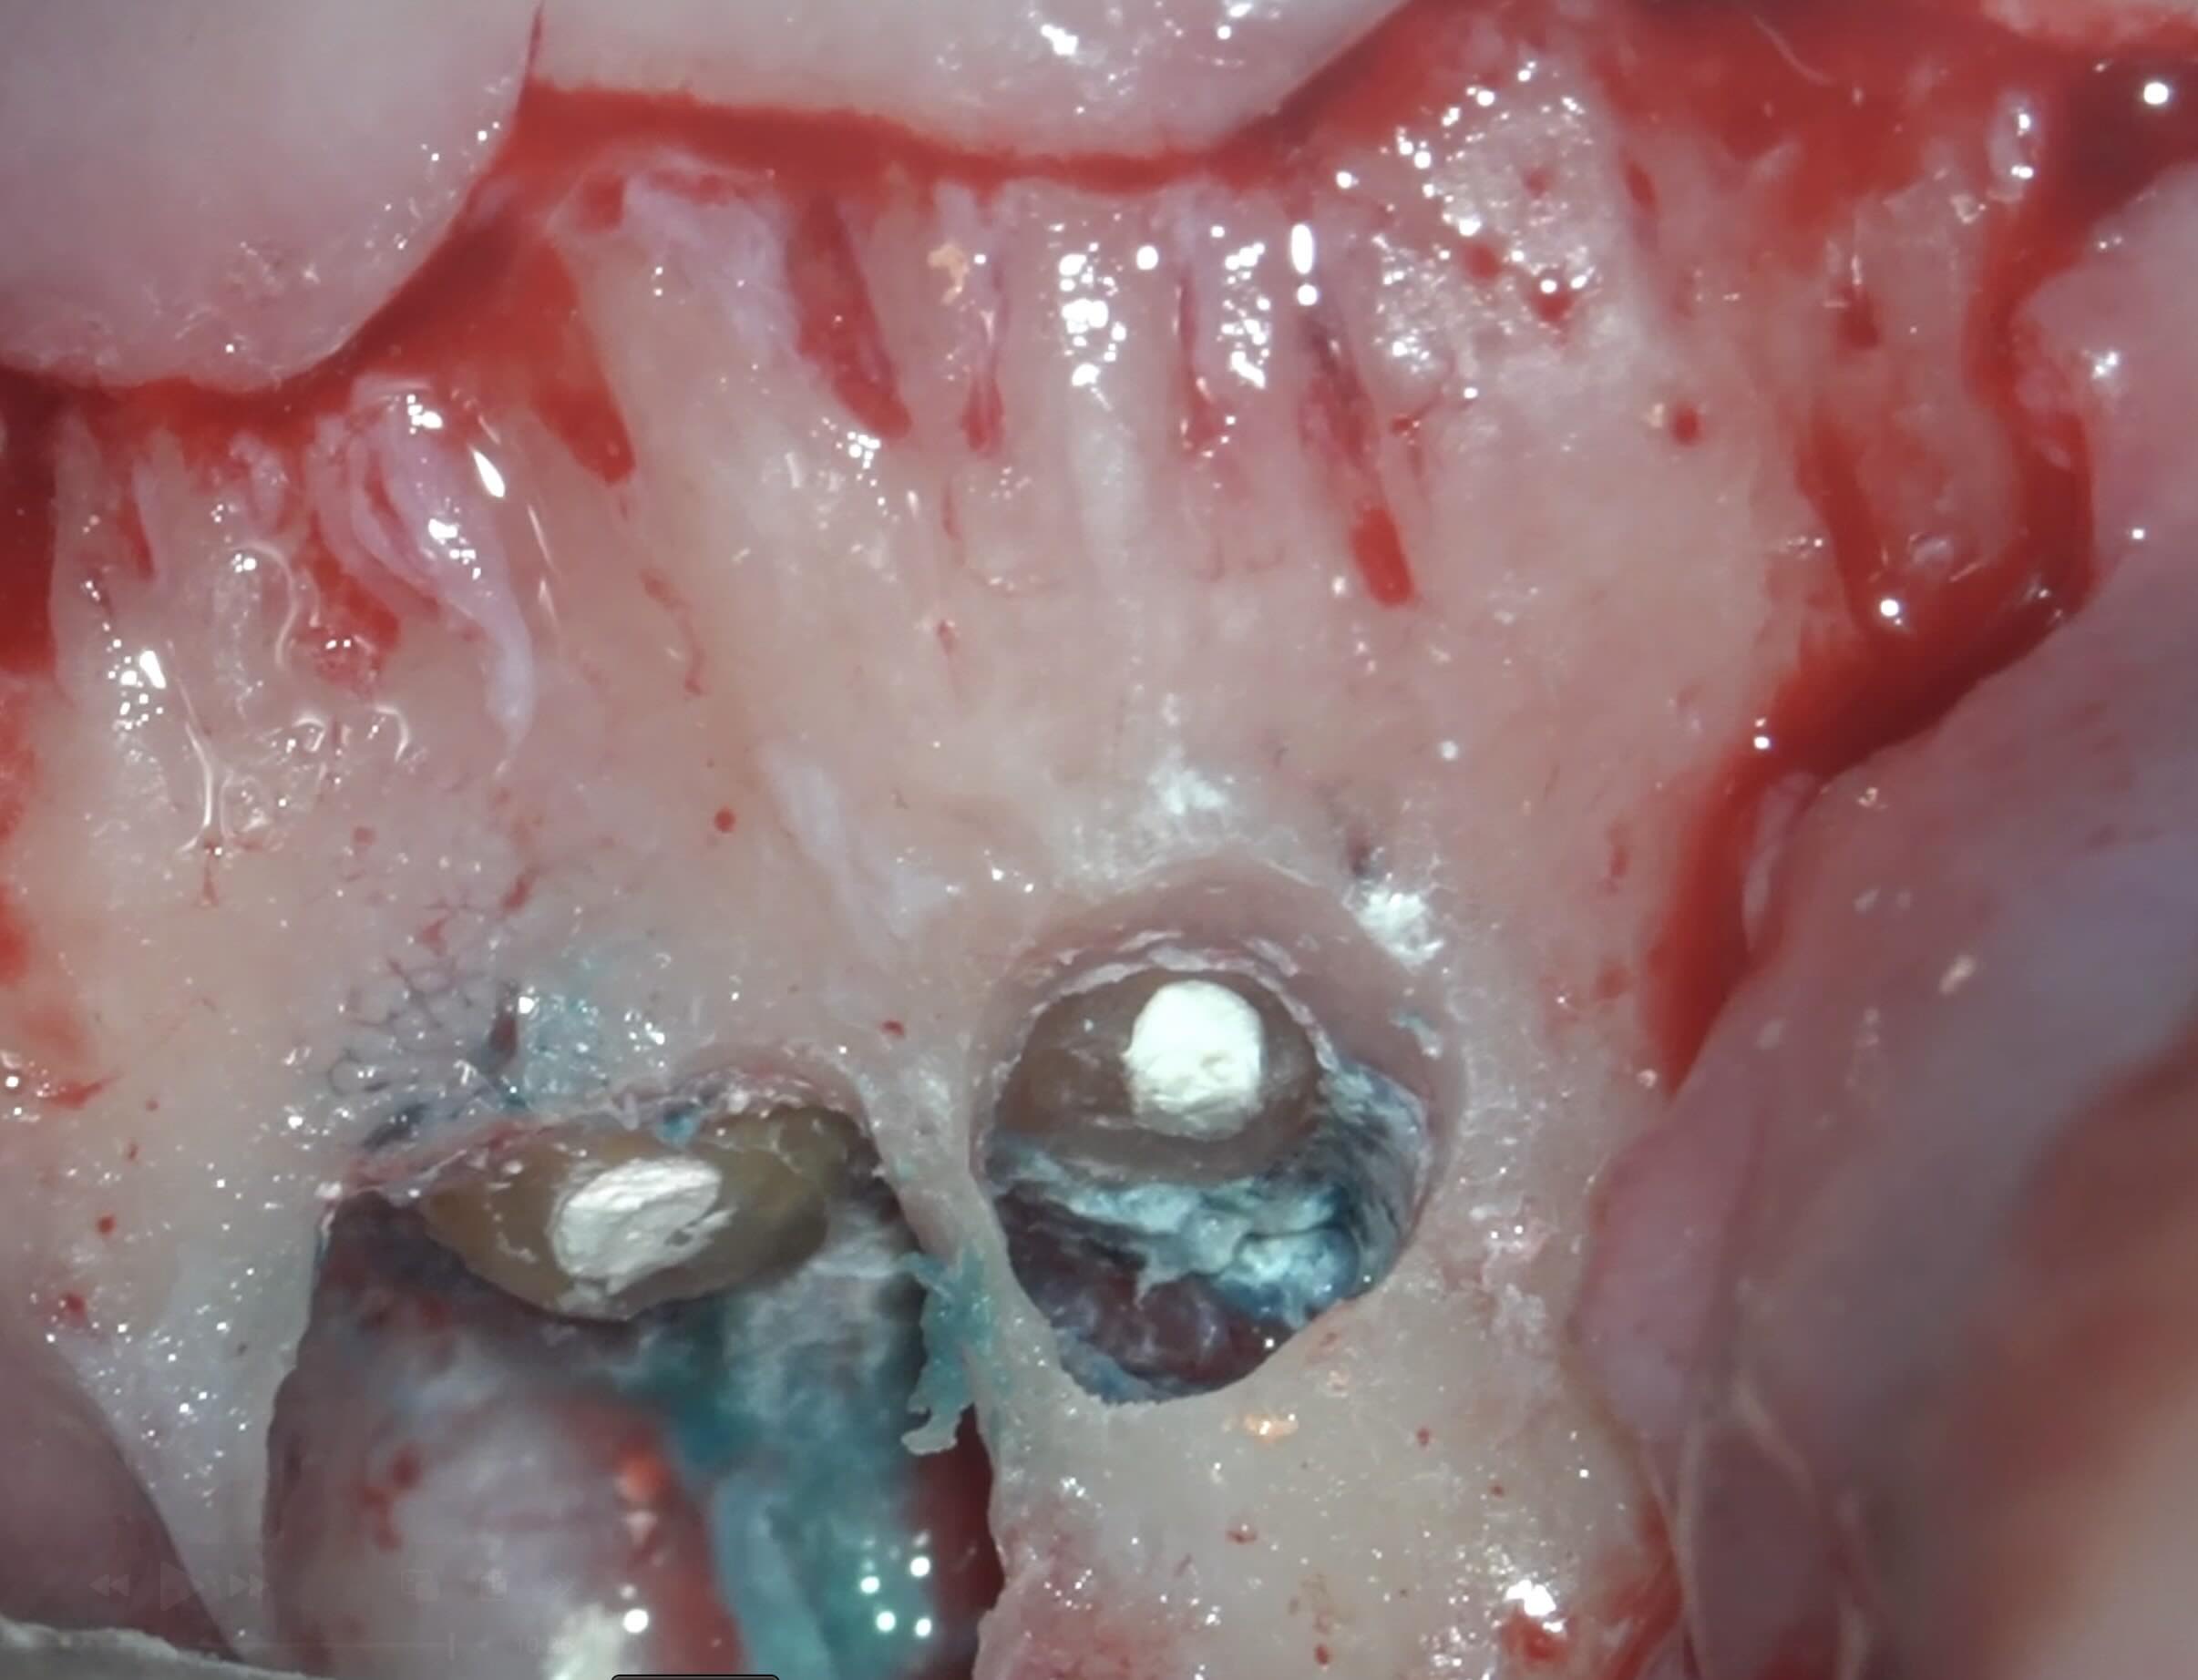

根尖部位を予測して、該当する骨を削除。

その後、歯根を約3mm切断。

それぞれの根管を確認

根の先を切るだけでは治りません。

その内部の感染を取り除く処置(逆根管形成)がとても重要になります。

これにより、根管内部の細菌数を減らしています。

根管形成後、しっかり封鎖をします。